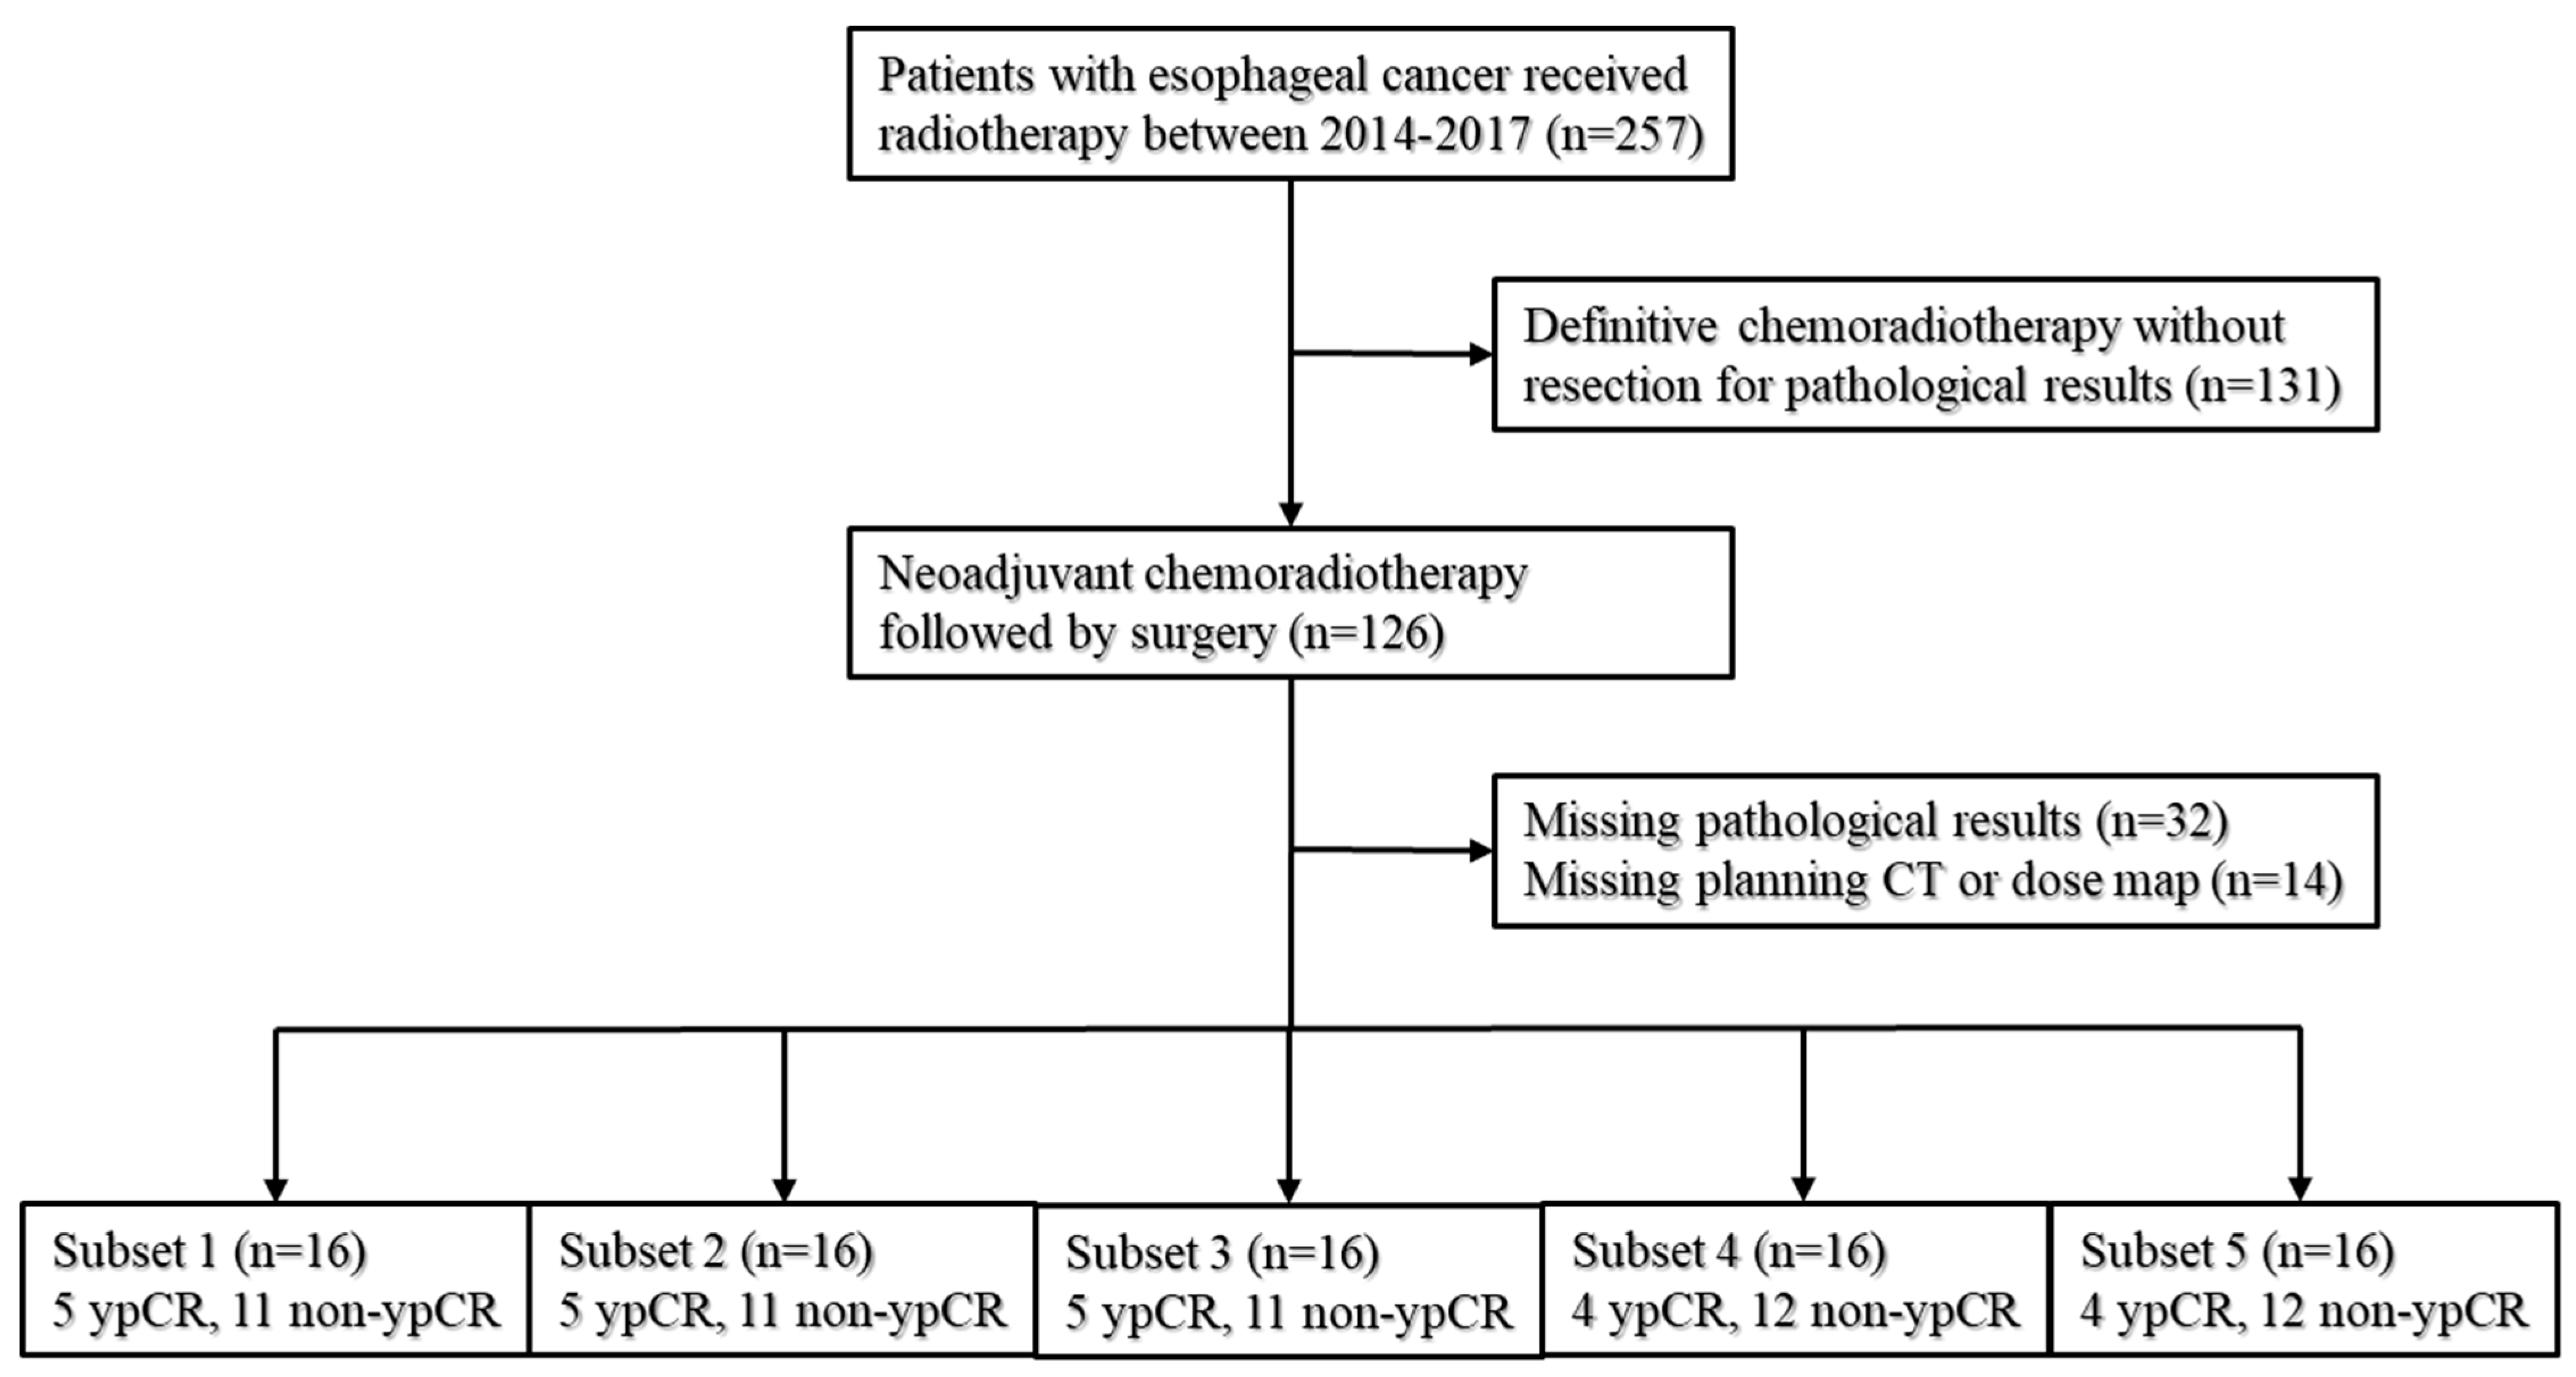

2.1. Patients

2.4. Five-Fold Cross-Validation